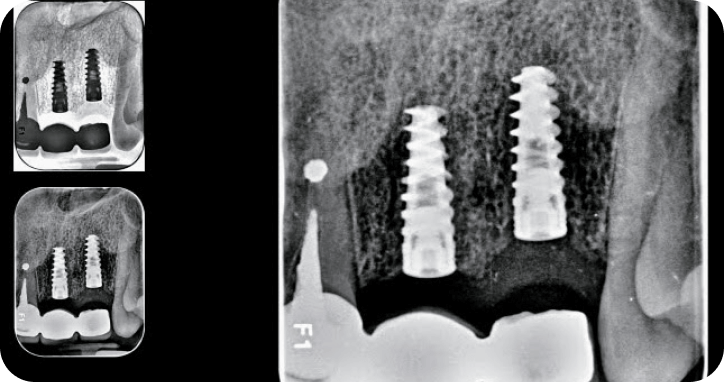

Casos